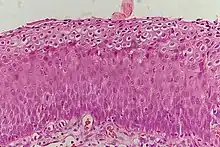

_normal_squamous_epithelium.jpg)

Historically, abnormal changes of cervical epithelial cells were described as mild, moderate, or severe epithelial dysplasia. In 1988 the National Cancer Institute developed "The Bethesda System for Reporting Cervical/Vaginal Cytologic Diagnoses".[12] This system provides a uniform way to describe abnormal epithelial cells and determine specimen quality, thus providing clear guidance for clinical management. These abnormalities were classified as squamous or glandular and then further classified by the stage of dysplasia: atypical cells, mild, moderate, severe, and carcinoma.[13]

CIN is classified in grades:[14]

| Histology Grade | Corresponding Cytology | Description | Image |

|---|---|---|---|

| CIN 1 (Grade I) | Low-grade squamous intraepithelial lesion (LSIL) |

|

![]() |

| CIN 2/3 | High-grade squamous intraepithelial lesion (HSIL) |

| CIN 2 (Grade II) |

![]() | |

| CIN 3 (Grade III) |